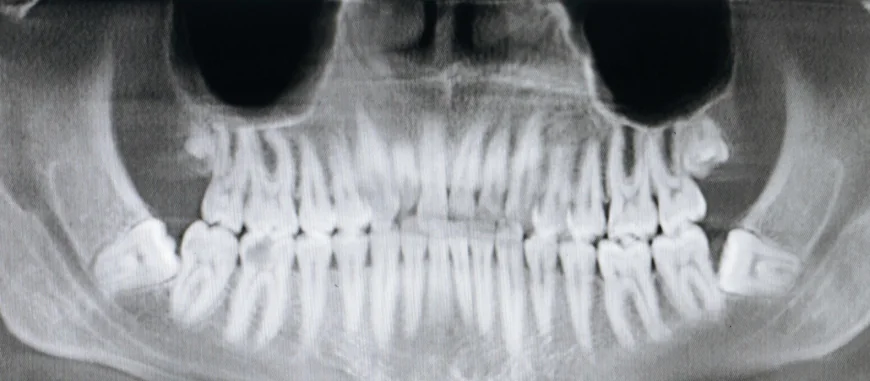

Panoramic dental X-rays provide a broad view of the teeth, jaws, nasal area, and sinuses. Unlike traditional X-rays that focus on a small section of the mouth, panoramic images offer a full overview, enabling dentists to detect issues that may otherwise go unnoticed. These images are especially useful for spotting impacted teeth, jaw disorders, bone abnormalities, cysts, and tumors.

Given the advantages, panoramic X-rays are commonly recommended for various dental procedures, from orthodontics to implants. However, cost considerations often come into play for patients, especially when factoring in the frequency of these scans.